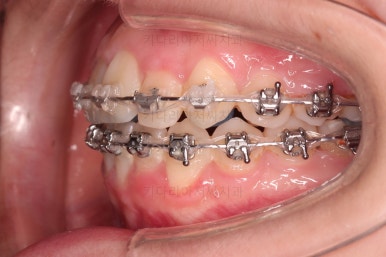

부산교정치료 초진 시 입안의 모습입니다.

치아가 전반적으로 삐뚤고, 덧니가 두드러져 보이네요.

그리고 선을 그려놨는데 윗니의 라인과 아랫니의 라인이 평행이 아니죠.

기울어 있어서 양측의 교합의 강도가 다른 상황이었습니다.

장치를 처음 부착한 사진입니다.

이번 환자분은 특징적으로 윗니의 장치와 아랫니의 장치가 다르죠.

윗니는 좀 더 심미적인 세라믹으로 선택하셨고 아랫니는 비교적 저렴하고 부피가 약간 작고 튼튼한 메탈로 진행했습니다.